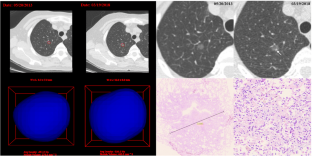

Between June 2012 and June 2019, 95 resected SSNs with preoperative long-term follow-up were enrolled in this retrospective study. SSN detection and segmentation were performed on preoperative follow-up CTs using the deep learning–based Dr. Wise system. SSNs were categorized into invasive adenocarcinoma (IAC, n = 47) and non-IAC (n = 48) groups; according to the interval change during the preoperative follow-up, SSNs were divided into growth (n = 68), nongrowth (n = 22), and new emergence (n = 5) groups. We analyzed the cumulative percentages and pattern of SSN growth and identified significant factors for IAC diagnosis and SSN growth.

Qi LL, Wu BT, Tang W et al (2020) Long-term follow-up of persistent pulmonary pure ground-glass nodules with deep learning-assisted nodule segmentation. Eur Radiol 30(2):744–755